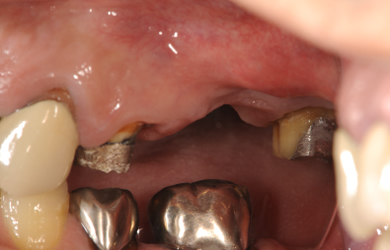

骨再生インプラント治療+セラミック治療

| カテゴリー | 【インプラント治療】【セラミック治療】 | ||||||||||||||||||||||||||||||||

| 性別/年齢 | 男性 / 50歳 | ||||||||||||||||||||||||||||||||

| 主訴 | 現在ムシ歯になっている箇所と、痛みのある部分の治療をセラミックで行って欲しい。 | ||||||||||||||||||||||||||||||||

| 治療方針 | ソケットリフト法により上顎洞底部を挙上することにより、骨の無い部分に骨をつくってあげ、インプラント治療を可能にする。 | ||||||||||||||||||||||||||||||||

| 治療内容 | インプラント2本(ソケットリフト)、メタルボンドセラミック5本、ハイブリッドセラミック2本 | ||||||||||||||||||||||||||||||||

| 総治療費 | 1,355,300円 | ||||||||||||||||||||||||||||||||

| 治療期間 | 海外から9ヶ月 |